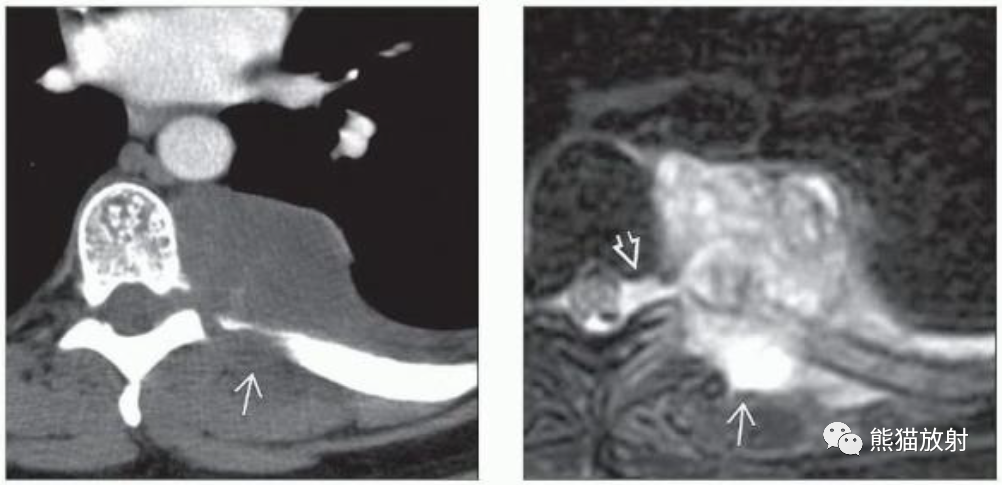

(左)同一患者,轴位T1WI MR显示边缘清晰的卵圆形肿块,均匀低信号。

(右)同一患者,轴位T2WI上整个肿块呈均匀高信号,未凸向椎管内生长。活检证实了神经鞘瘤的诊断。周围神经鞘瘤通常无症状,可能在因其他原因检查时偶然发现。

(左)39岁男性,严重背痛。轴位CECT显示左侧椎旁区域软组织肿块包围并侵犯相邻的左后肋,并相邻的椎间孔扩张。

(右)同一患者,轴位T2WI显示不均匀的高信号肿块,边缘不清晰,可见胸壁侵犯和相邻左侧椎间孔扩张。活检证实为MPNST。